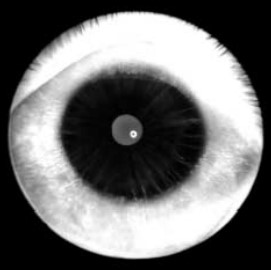

- По мере развития заболевания в пигментном листке появляются и прогрессируют сквозные дефекты, приводя в тяжелых случаях к аниридии с визуализацией неизмененных цинновых связок.

Исходно имеет место недоразвитие стромы и аномальная гипертрофия пигментного листка (в 34,5 раза выше нормы), что ведет к снижению прочности и эластичности радужки. Было выявлено, что постепенно происходят механическое растяжение и разрывы радужки, уменьшается ее площадь, но резко увеличивается толщина. Это сопровождается эктопией зрачка, затем появляются тонкие радиальные дефекты периферии пигментного листка, которые постепенно увеличиваются до огромных сквозных треугольных отверстий основанием к лимбу.

У больных нередко имеются аномалии зрачка: дистопия, неправильная форма, гипертрофия или отсутствие пигментной каймы. Схожесть внешних изменений радужек, их последовательность и типичность создают впечатление близкого родства совершенно несвязанных между собой пациентов.